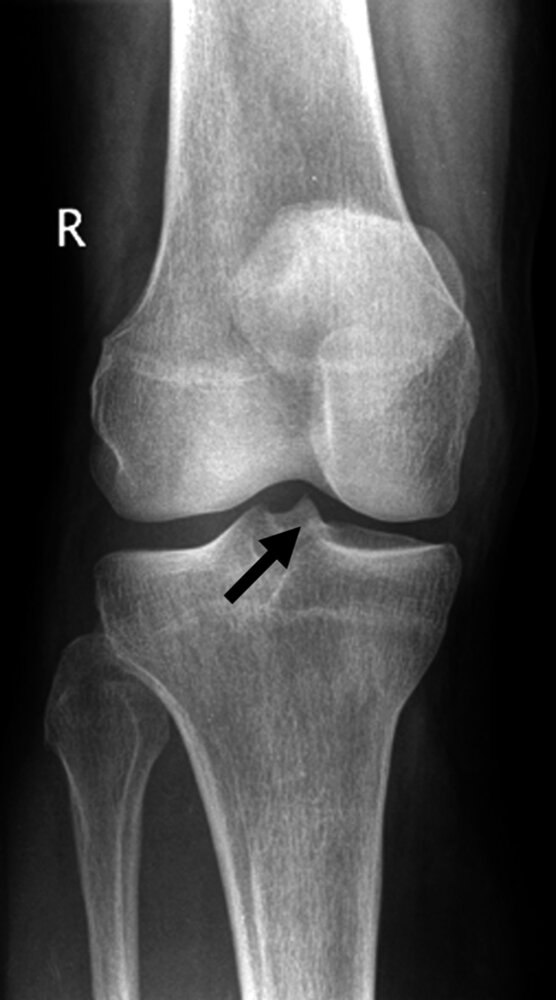

27. The arrow in the X-ray image shown marks the bone attachment, origin, or anchoring point of the:

A. Anterior cruciate ligament (ACL)

B. Patellar ligament

C. Popliteus muscle

D. Soleus muscle

E. Iliotibial tract